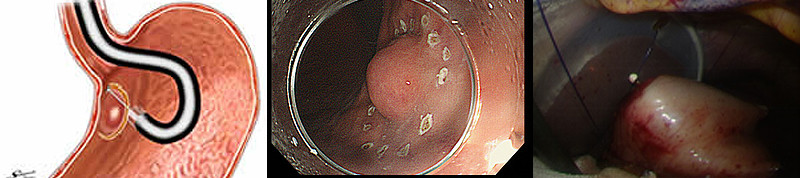

当科では、腫瘍の大きさが5cm以下の場合には、従来より腹腔鏡を用いた外科手術を行っております。腹腔鏡手術は開腹手術と比べておなかの傷を小さくでき、術後の痛みが少なく回復が早いという利点があります(図1)。さらに最近ではGISTに対し、胃内視鏡と腹腔鏡を組み合わせたLECS(Laparoscopy Endoscopy Cooperative Surgery:腹腔鏡・内視鏡合同手術)を導入し、良好な結果を得ています(図2)。特に胃内発育型のGISTに対する従来の腹腔鏡のみを用いた手術では、正常な胃壁の余分な切除範囲が大きくなり、術後に胃の変形を来すことがありました。LECSでは、消化器内科医が胃内視鏡を用いてGIST周囲の胃壁を切ることにより、正常胃壁の切除を最小限にとどめることができます。また、胃の入り口近くにGISTが存在する場合には、従来法では噴門側胃切除(胃の上部を1/2程度切除する方法)が必要でしたが、LECSを用いることにより部分切除が可能となりました。腫瘍を切除した後は、腹腔鏡手術にて胃壁を縫合閉鎖します。この方法により、最小限の胃部分切除が可能となり、また術後の胃の変形を来しにくくなりました(図3~4)。

図3 LECSの流れ

- 1.内視鏡操作(消化内科医により胃カメラで胃の粘膜側(内側)から腫瘍周囲を切開します)

- 2.腹腔鏡操作(消化器外科医により腹腔鏡下に胃の漿膜側(外側)から腫瘍周囲を切開します)

- 3.胃壁の閉鎖(消化器外科医により腹腔鏡下に胃の切除部分を縫合閉鎖します)

図4 摘出標本 約2cmの大きさの胃GIST